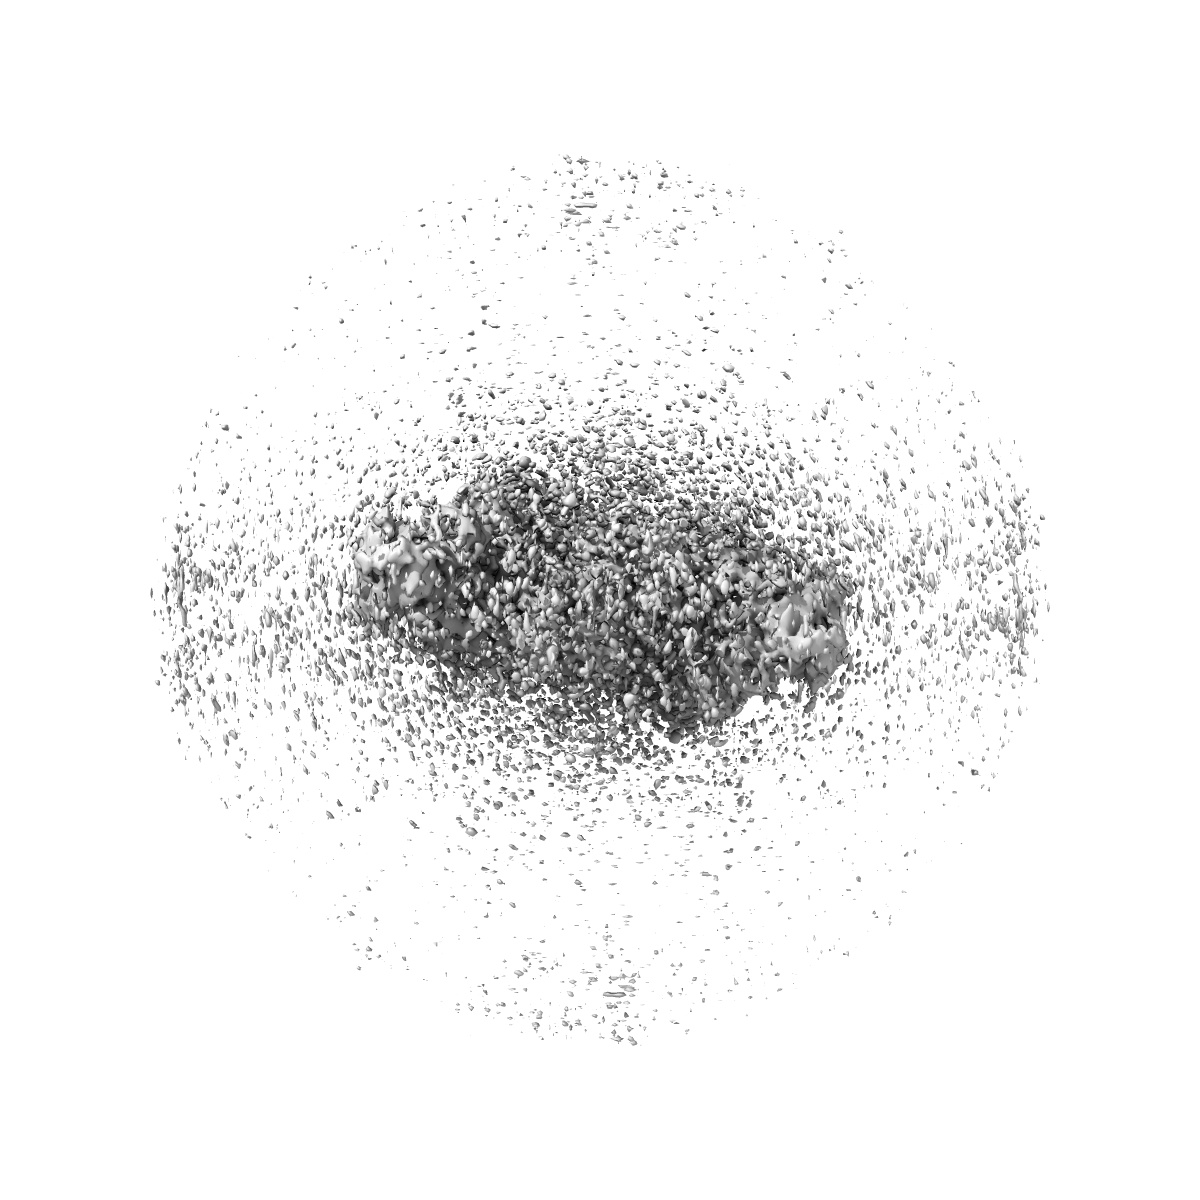

Cryo-EM structure of MPXV core protease in complex with aloxistatin(E64d)

Single-particle2.93 Å

Sample: PROTEASE DIMER

Substrate recognition and cleavage mechanism of the monkeypox virus core protease.

(2025) Nature , 643 , 271 - 279